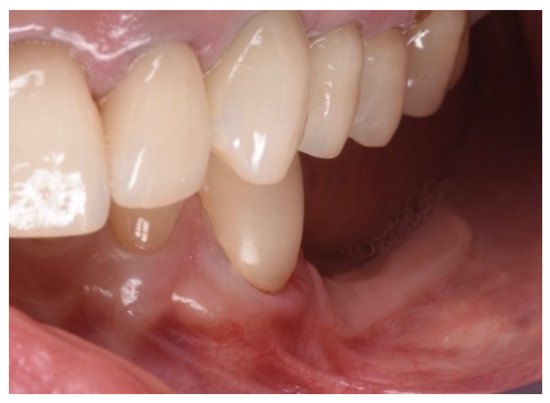

Figure 10.

Clinical evaluation after 18 months of prosthetic loading.